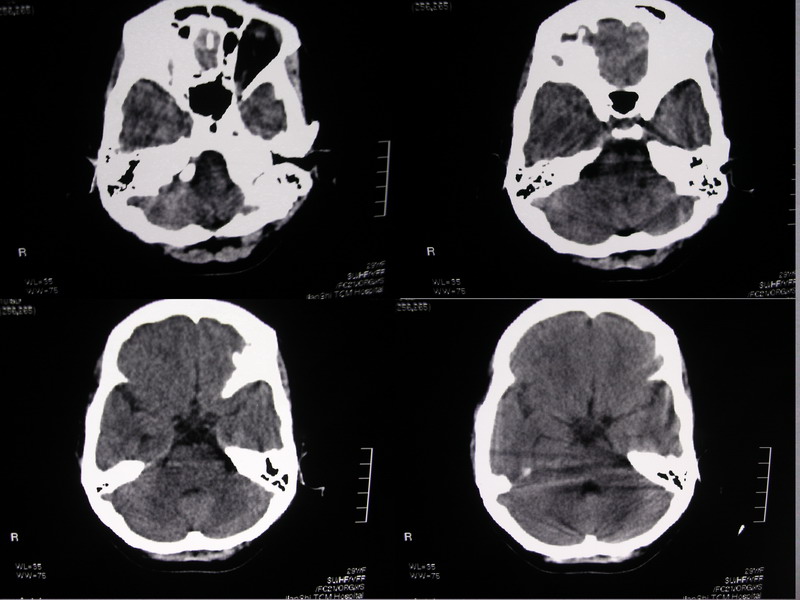

向××,女,29岁,二十天前高热,抗炎治疗后双眼斜视,肌无力,双下肢张力ii级。

奇怪啊!临床症状那么典型,为什么没有什么脑炎的迹象?二十天了,应该有表现的,是我眼拙?但小脑蚓部以及左侧颅中窝均属正常我应该没有看错,大汗淋漓!渴望老师们指点迷津!

除侧脑室额角轻度扩大外,余未见异常。

感觉胼胝体有异常,但看不出异常影像特征,建议行mri进一步确诊.